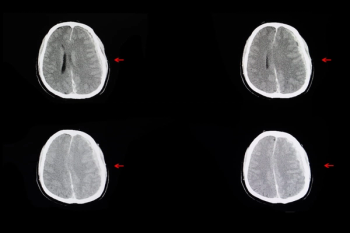

Offering comparable sensitivity to radiologists for detecting contralateral breast cancer on mammography images, an emerging adjunctive AI software may also facilitate earlier diagnosis, according to study findings presented at the at the 2024 American Society of Clinical Oncology (ASCO) Annual Meeting.